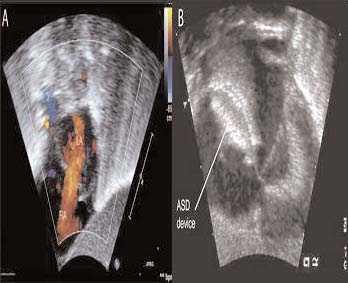

Fig. 2. A la izquierda, en A, se muestra la ecocardiografía transtorácica con flujo Doppler color del paciente antes del cierre de la CIA con el dispositivo. Obsérvese el cortocircuito significativo (chorro naranja) de la aurícula izquierda a la derecha. A la derecha, en B se muestra el dispositivo en posición apropiada en el tabique auricular, ocluyendo la CIA. Es importante destacar que el dispositivo ha capturado el tejido septal auricular entre sus dos discos. RA: aurícula derecha; LA: aurícula izquierda.

En el momento del procedimiento, el peso del lactante era de 2,3 kg. Con el lactante sedado y paralizado, respirando un 35% de oxígeno, se obtuvo un acceso vascular femoral y se efectuó un cateterismo cardíaco derecho e izquierdo anterógrado. Mediante pulsioximetría, se puso de relieve un cortocircuito izquierda a derecha significativo, con un cociente de flujo pulmo-nar/sistémico mayor que 3, hipertensión pulmonar y desaturación venosa pulmonar. Además, se identificó un aumento de las presiones diastólicas ventriculares derechas con insuficiencia cardíaca derecha a partir de la sobrecarga de volumen. Durante el procedimiento, el lactante recibió heparina (100 U/kg) y cefazolina (25 mg/kg). Se modeló un catéter Arrowflex de 22 cm y calibre 6 (Arrow International Reading, MA) para acceder perpendicularmente al tabique auricular, y se hizo avanzar desde la vena femoral. La ecocardiografía transtorácica simultánea demostró un diámetro no desplegado del defecto de 5,5 mm, y un cortocircuito izquierda a derecha (fig. 2a). Se seleccionó un dispositivo Amplatzer Septal Occluder de 6 mm (AGA Medical Golden Valley, MN) y se desplegó a través del defecto. Con el cable de distribución todavía unido al dispositivo, se observó un desplazamiento caudal significativo del tabique auricular. Sin embargo, la ecocardiografía demostró que el dispositivo se asentaba apropiadamente con el tejido septal auricular capturado entre su parte auricular izquierda y derecha (fig. 2b). Tras la liberación del dispositivo del cable de distribución, tanto aquél como las estructuras cardíacas recuperaron una orientación más normal. Al cabo de 24 horas, la radiografía de tórax demostró una mejora sustancial de la congestión pulmonar y la normalización de la cardiomegalia (fig.1b). El lactante pudo desconectarse rápidamente del ventilador emprendiendo la extubación a los tres días del procedimiento.